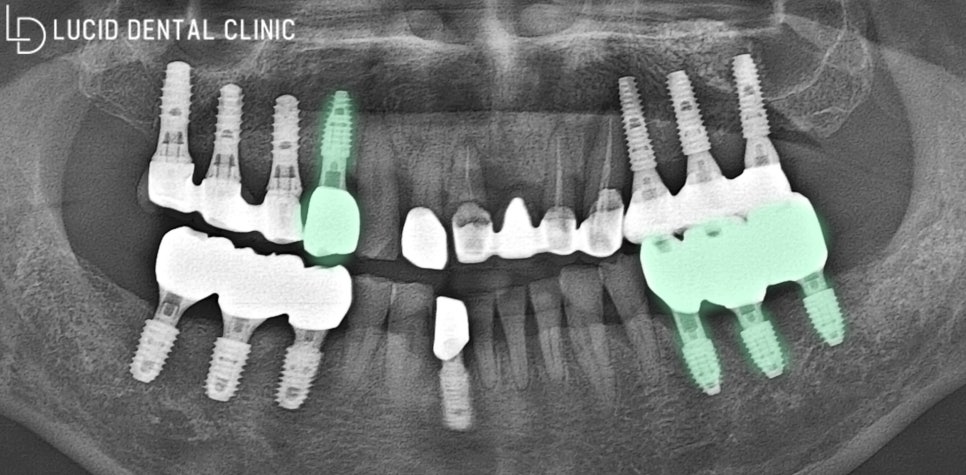

- 임플란트 수술 종료

아래 사진과 같이 보철 체결과 동시에

계획한 모든 치료 과정을 마쳤습니다.

이전보다 튼튼하고, 통증 없는 구강 환경에

환자께서도 크게 기뻐하고 가셨는데요 ㅎㅎ